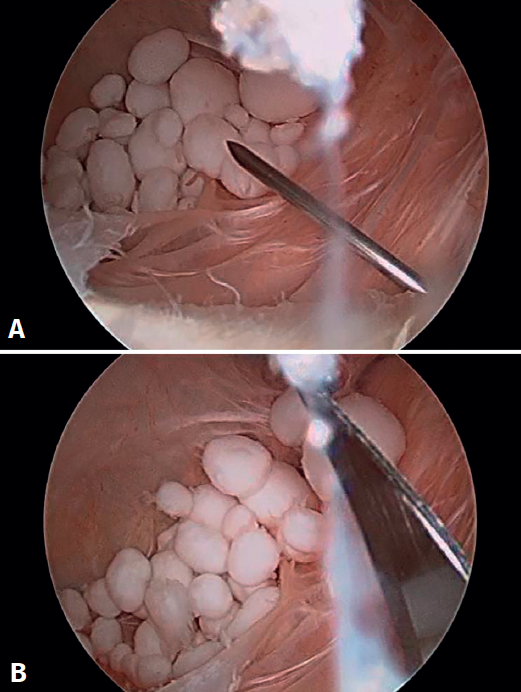

Inicialmente, se realizó una artroscopia diagnóstica a través de los portales anterolateral y anteromedial estándares, en la que se identificó una rotura degenerativa del menisco medial, que se regularizó con instrumental motorizado y vaporizador de radiofrecuencia. A continuación, se realizó un portal posteromedial bajo visión directa intraarticular, para explorar el compartimento posterior de la rodilla. Durante la exploración, se localizó el orificio de entrada del quiste poplíteo, cerrado por una capa de tejido sinovial, que fue desbridado con instrumental motorizado a través del portal posteromedial. Esto permitió acceder al interior del quiste de Baker, donde se hallaron múltiples cuerpos libres de aspecto y consistencia cartilaginosa (Figura 2). Dada la dificultad de acceso a dichos cuerpos libres, se decidió la realización de un portal transgastrocnemio (Figura 3): bajo visión directa, con la óptica en el portal posteromedial habitual, se marcó el punto de entrada al quiste con una aguja Abbocath® a través del gastrocnemio medial. El portal se situó en la región proximal del gastrocnemio, a la altura aproximada de la localización del quiste –determinada por la combinación de palpación y visualización directa con el artroscopio–, desde el lado medial para evitar las estructuras neurovasculares poplíteas. Una vez colocado el Abbocath® como guía en la posición deseada, se procedió a la realización del portal mediante una incisión longitudinal de 0,5 cm con bisturí del n.º 11. Este abordaje facilitó el acceso al interior del quiste, pudiéndose realizar la exéresis de los cuerpos libres previamente identificados de forma extraarticular directa, evitando así la diseminación dentro de la articulación (Figura 4). Finalmente, se realizó un desbridamiento de las paredes del quiste a través del mismo portal transgastrocnemio (Figura 5). El material resecado se envió para su estudio anatomopatológico.